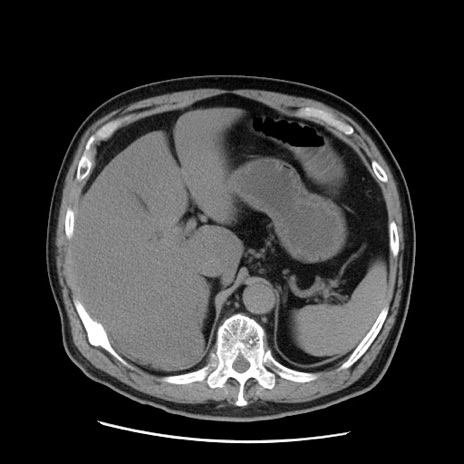

症例20(横断像)

【症例】 60歳代男性

【主訴】 腹部膨満、嘔吐

【現病歴】5日前頃より倦怠感を認め食事量減少し4日前の朝嘔吐、食事摂取困難となった。 3日前近医受診し点滴施行され整腸剤などを処方された。 当日他院を受診し、腹部膨満著明、炎症反応の上昇(CRP10.8、WBC11200)あり、紹介受診となる。

【身体所見】 意識JCS1 受け答えがはっきりしないBP 111/57mHg、 P 67bpm、、BT35.2°C、SpO2 97%(RA)、 腹部:膨隆、打診で鼓音あり、全体的に圧痛有り、腸蠕動音(-)、反跳痛ははっきりせず。

【データ】WBC 11400、CRP 14.20